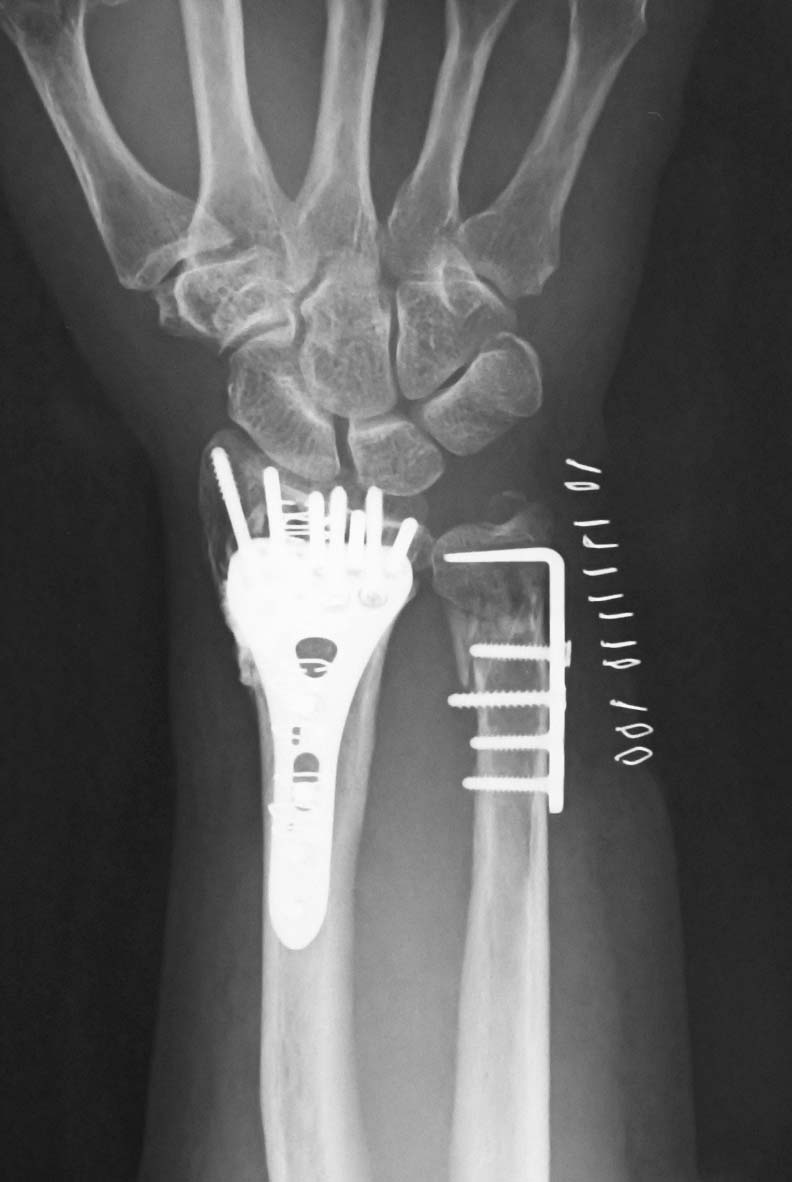

先日、橈尺骨遠位端骨折に対して骨折観血的手術を施行しました。下図のように、橈骨・尺骨とも非常に不安定性が強かったので、尺骨にも骨接合術を計画しました。

尺骨に使用する内固定材料のひとつとして、フックプレートがあります。今回使用したのは、HOYAが販売しているStellar 2のフックプレートです。

このプレートはロッキングですが、遠位部がフックになっていることが特徴です。橈骨遠位端骨折用のStellar 2のオプションとしての位置づけですが、こちらの方が有用です(笑)。

かなり粉砕した粗鬆骨だったので固定性が心配でしたが、さすがフックプレートだけあって、尺骨遠位端に関しても比較的しっかりした固定を得ることができました。

手術手技も非常に簡便で、ガイド越しに仮固定用のK-wireを刺入するだけで、あっという間に内固定が終了しました。コストパフォーマンスの高い手術だという印象です。

今回の症例のように、尺骨の遠位で骨折していて不安定性が高い場合には、フックプレートを使用することも、治療の選択肢のひとつではないかと感じました。